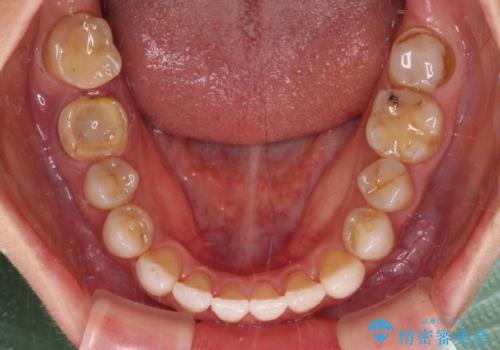

- 上下前歯の開咬とデコボコを気にして来院された患者様です。

開咬(オープンバイト)はインビザラインによる矯正治療がワイヤー装置と比べて圧倒的に有利であるため、インビザラインによる矯正治療を行うこととしました。

通院されなかった時期があって治療期間が長くなったり、奥歯に抜歯が必要な歯があったりと、治療は一筋縄にはいきませんでしたが、何とか治療を終えることができました。

今後はインプラント治療やむし歯治療を進めて行く予定です。